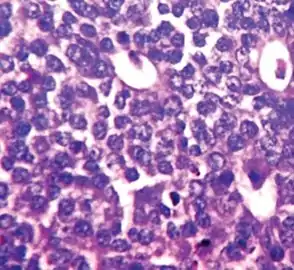

Invasive lobular carcinoma with moderate nuclear pleomorphism.